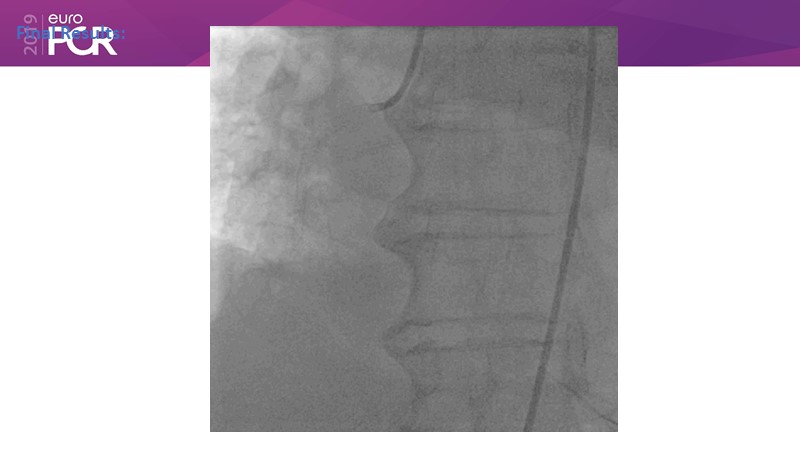

Ability to treat diabetic patients: DES + DCB strategy

Consult this session to get insights about the need for a dedicated drug eluting stent (DES), as well as the benefits of a DES+DCB strategy, for diabetes mellitus (DM) and acute MI (AMI) patients.

- To understand and learn benefits of DES+DCB strategy to provide uniform and homogenous drug delivery in patients with diabetes mellitus and acute MI

- To learn about a DES with on label indication for diabetes mellitus and acute MI